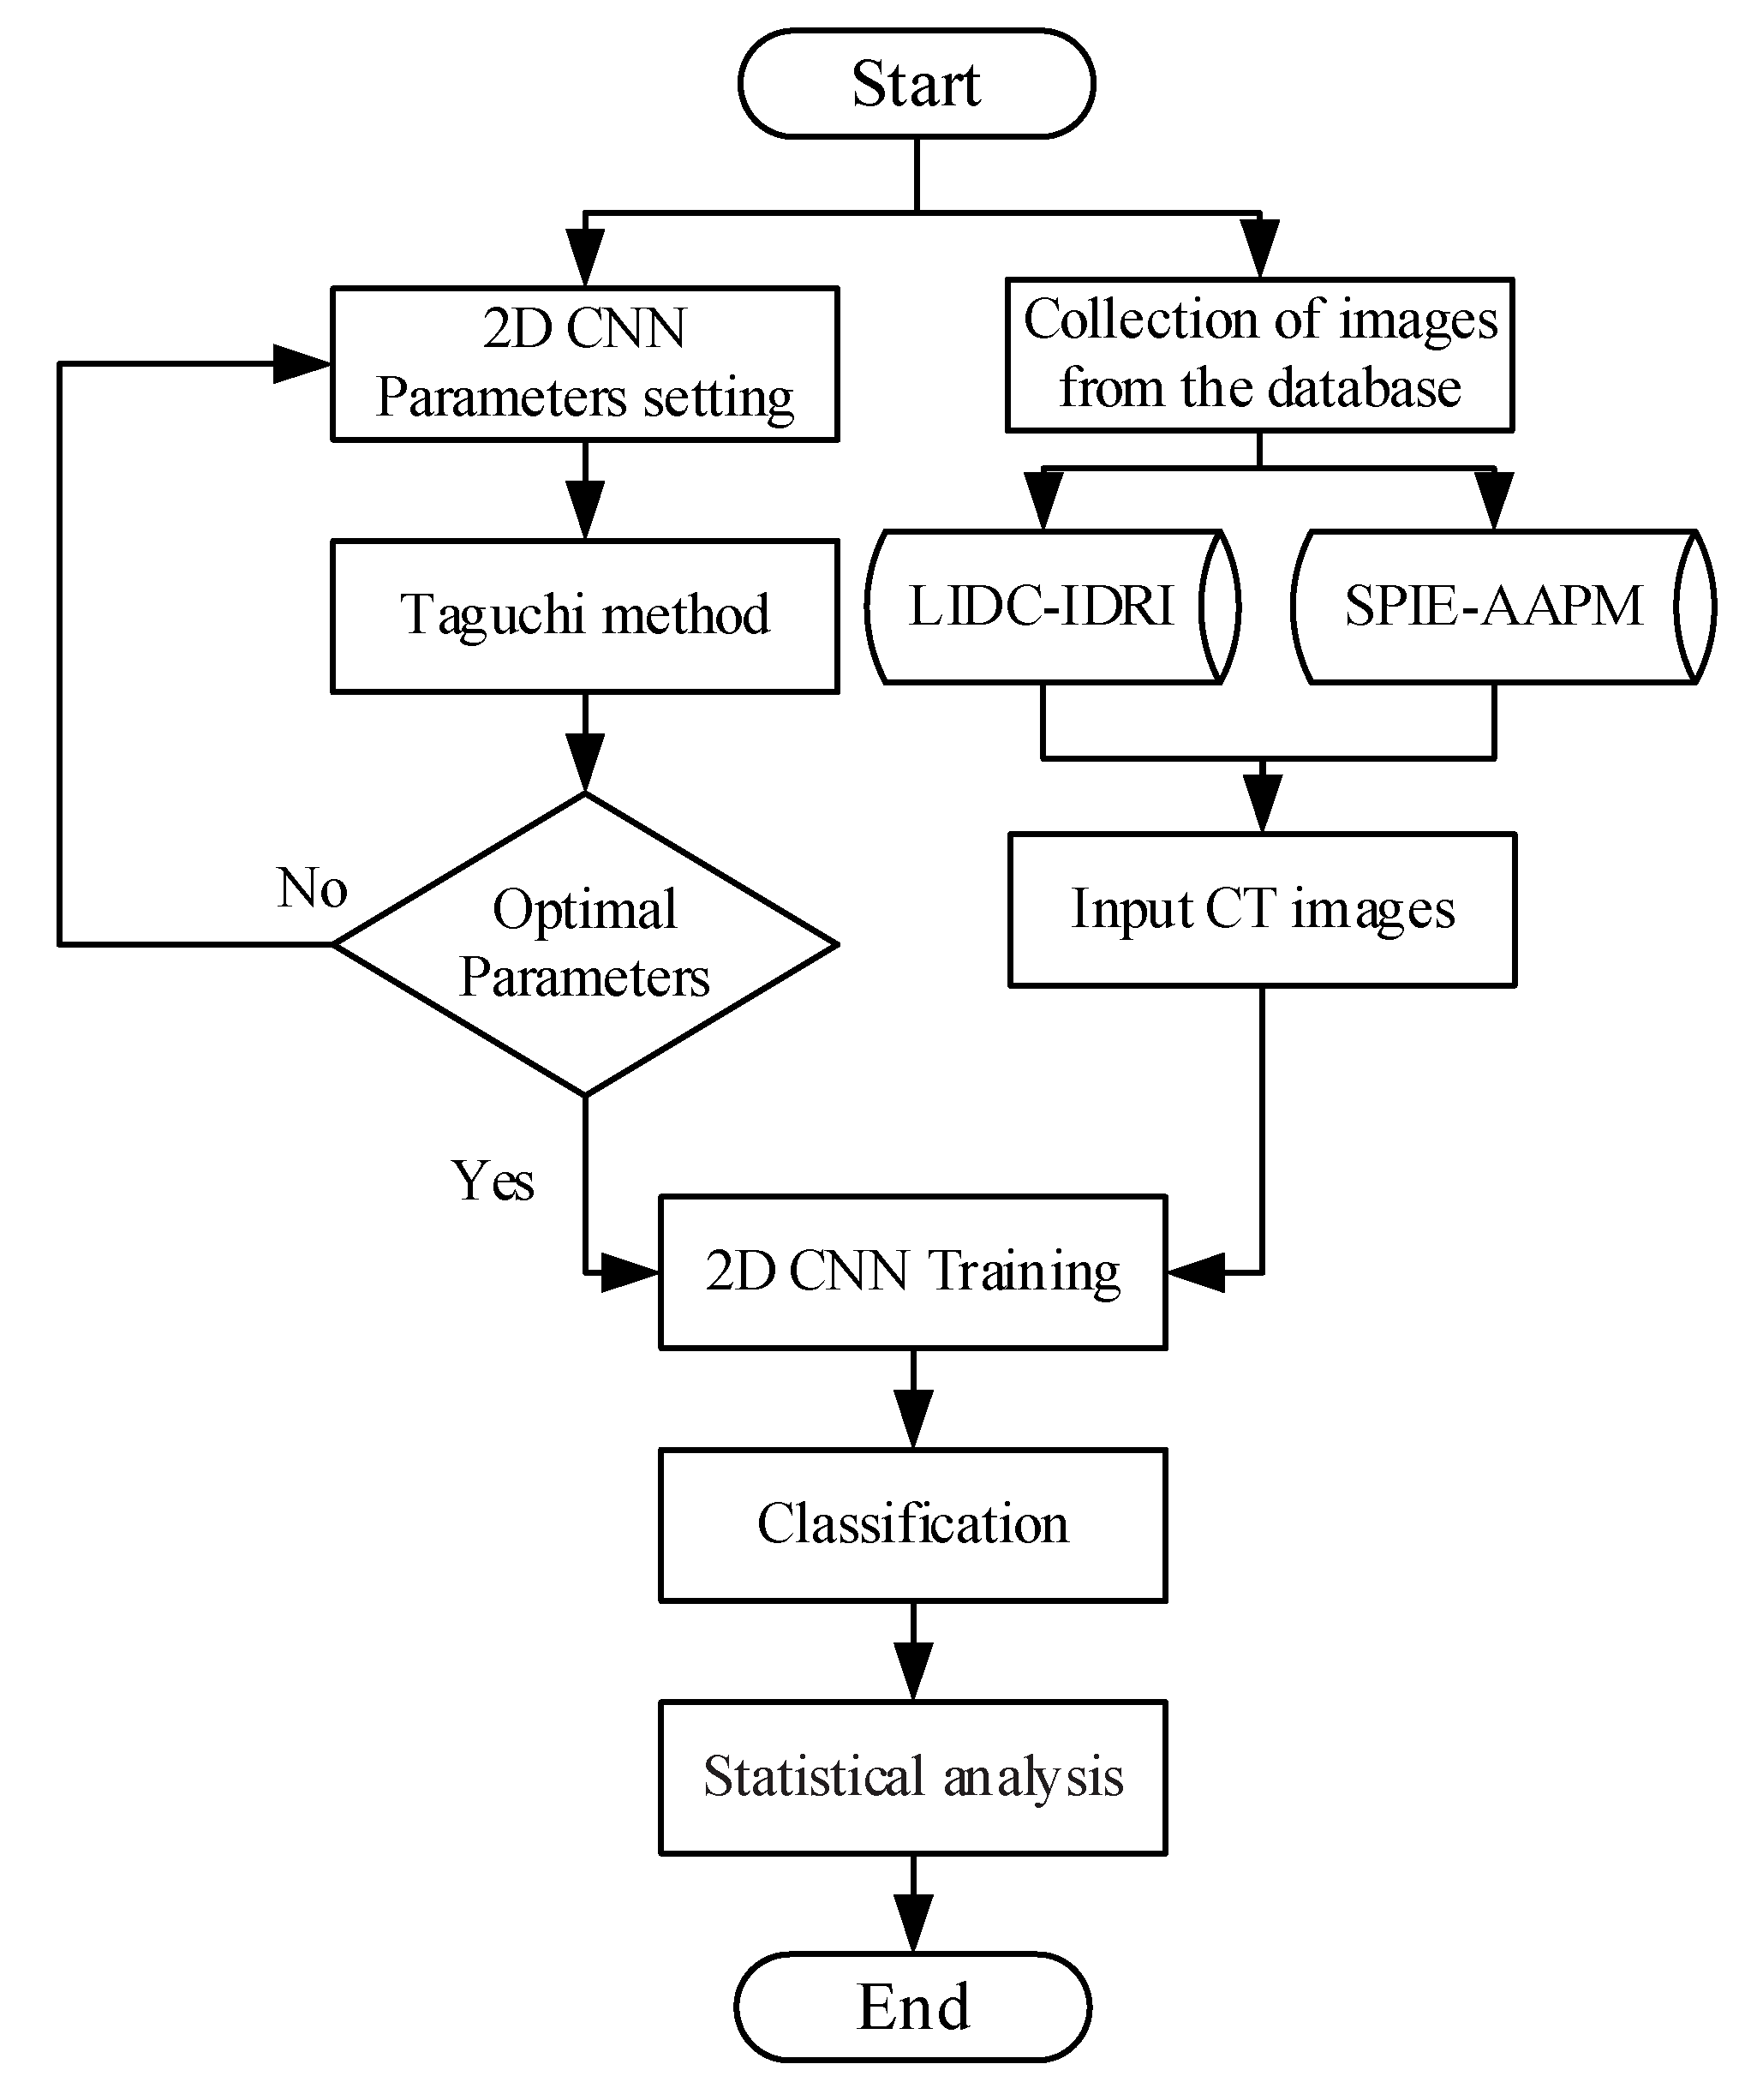

2. Methods

2.1. Taguchi Method

2.2. Materials

2.3. 2D CNN Model